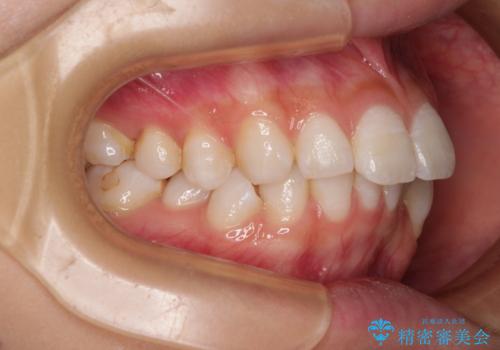

- 口を閉じたときに飛び出してしまう上顎前歯を気にして来院された患者様です。

下顎はデコボコが気になっていたため、上下左右第一小臼歯4本を抜去して、ワイヤー装置にて口元の突出感を改善するよう矯正治療を行うこととしました。

下唇に前歯が当たって跡が残ってしまう状態でしたが、スッキリとした口元に仕上げることができました。